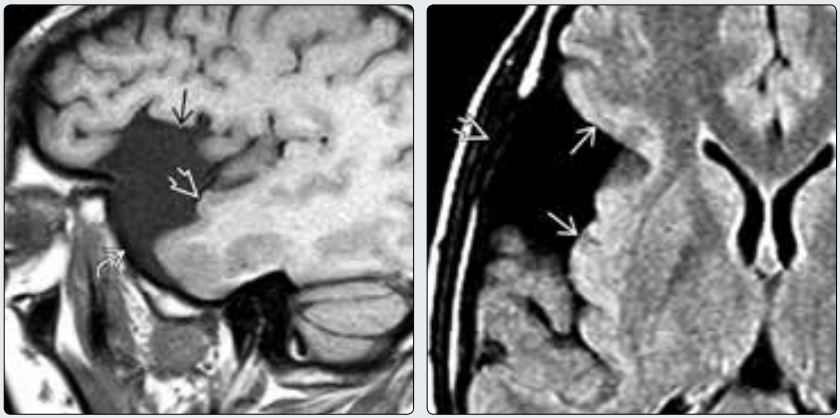

(左图)MR矢状位T1WI显示典型的颅中窝蛛网膜囊肿→。注意蝶骨大翼↪扩大延展,以及颞叶⇒向后移位。(右图)同一患者的横断位FLAIR 显示蛛网膜囊肿呈典型的“四边形”,边界清晰,边缘光滑,相邻皮质受压移位→。注意囊肿邻近的颅骨变薄⇒